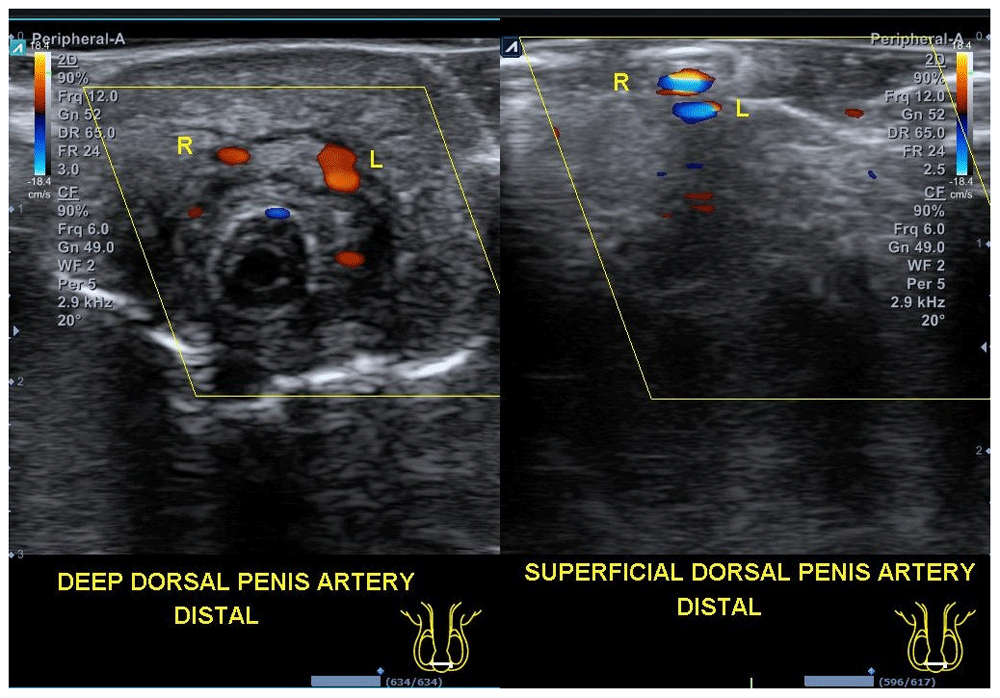

The patient was put on total bed rest until the third day post-surgery, with administration of intravenous 3rd generation cephalosporine antibiotics (ceftriaxone 2gr/day), an analgesic (Ketorolac 25mg twice a day), and penile phototherapy (six hours a day) for five days. Five days after reconstruction, the penis showed no significant edema and swelling of the distal penile shaft, and sensation started to return gradually. Evaluation with Doppler ultrasound showed adequate deep and superficial arterial flow at the distal end of the penis. On the fifth day post-surgery, the patient was discharged without urethral catheter following spontaneous micturition (Figure 2).